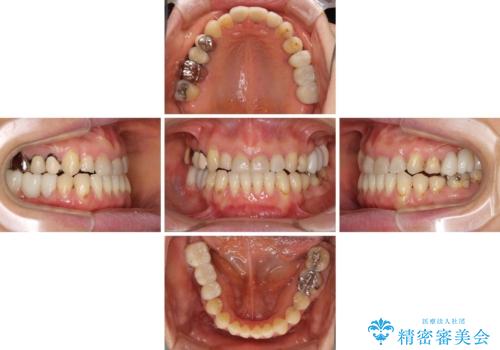

反対咬合や欠損を治療したい インビザライン矯正とオールセラミックブリッジ

- 虫歯治療がうまく進まないとのことで来院された患者様です。

虫歯治療や欠損補綴治療も必要でしたが、前歯が反対咬合であったので、セラミッククラウンやブリッジによる治療と並行して矯正治療を提案しました。

仕事柄海外出張が多いとのことで、虫歯治療後にインビザラインにて矯正治療を行うこととしました。

海外出張にとどまらず海外赴任もあり、途中2度の妊娠もあったため、治療には非常に長い期間を要することとなりました。